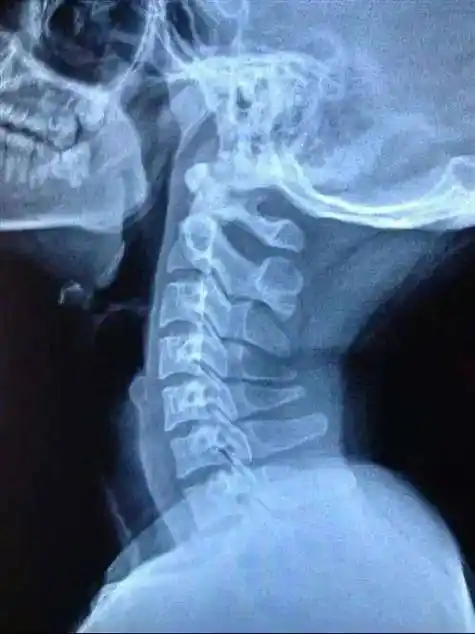

16615久卧对于不到3个月的宝宝来说,颈椎刚刚发育,如果长时间

颈椎处有凹陷正常现象图片

幼小!颈椎曲度变直是怎么回事?"大吉大利"-第1张图片-丸子博客

每晚奋战作业到深夜这个11岁孩子颈椎提前老化